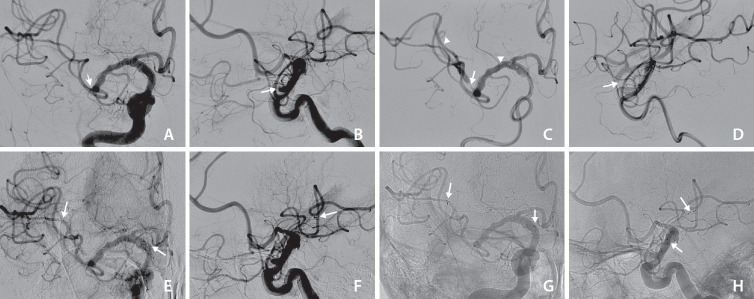

Mechanical thrombectomy using a stent retriever is a widely-used technique for recanalizing occluded cerebral arteries in acute ischemic stroke. Although rare, inadvertent stent detachment has primarily been reported with earlier stent retriever designs. We present 2 cases of inadvertent stent detachment with the pRESET stent. In the first case, an elderly patient presented with right middle cerebral artery occlusion and experienced stent detachment during the second retrieval. Despite this, successful recanalization was achieved through balloon angioplasty. In the second case, an elderly patient experienced stent detachment after the third retrieval, and recanalization of the M1 segment was unsuccessful due to the inability to pass the microcatheter. The first patient had a modified Rankin scale (mRS) score of 3, while the second had a poor prognosis with an mRS score of 5. These cases highlight that inadvertent stent detachment can impact outcomes, and balloon angioplasty may serve as a useful salvage therapy.